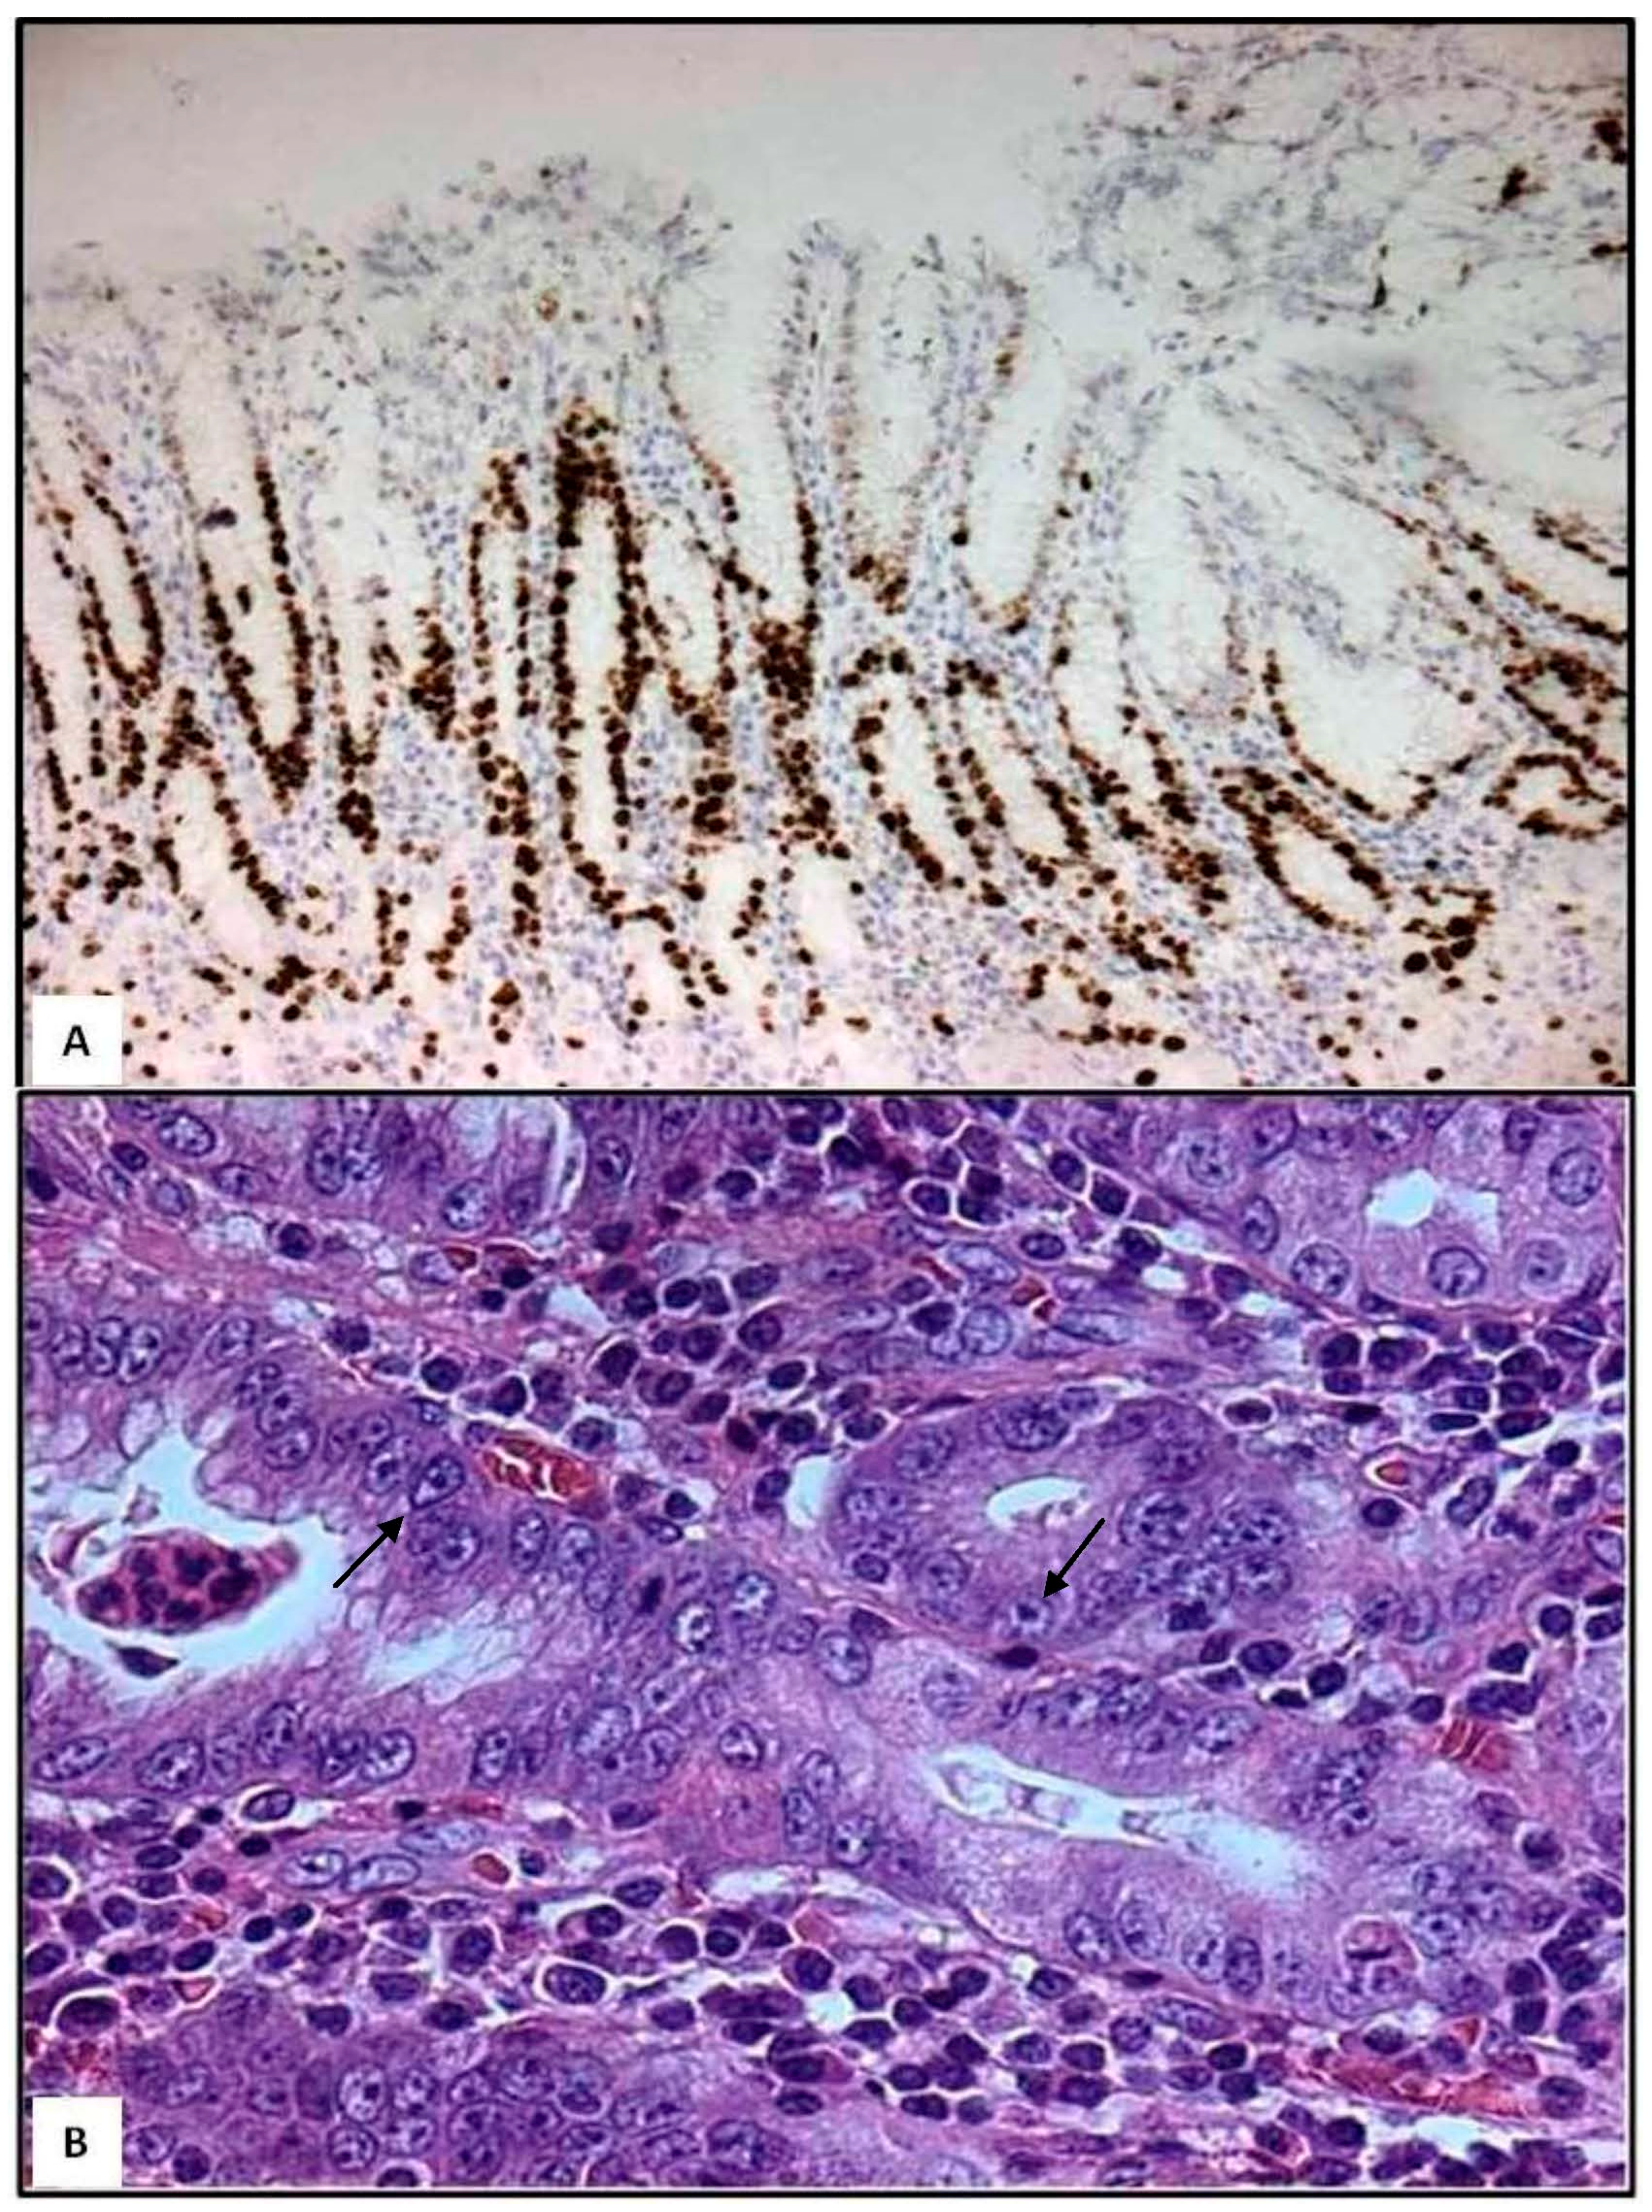

Following the progression of H. pylori gastritis, gastric mucosa acquires irregular morphology due to crowding of pits [9]. Moreover, by Ki-67 immunohistochemistry, an increased proliferation is found in the gastric mucosa of bioptic specimens [9]. In detail, cycling epithelial cells are found at the isthmus/neck region and at the deep portion of the pits (Figure 1A); this proliferative zone appears elongated and constituted by epithelial cells showing enlarged nuclei, prominent nucleoli, and loss of cytoplasmic mucins (Figure 1B). From a histopathological viewpoint, presence of neutrophils characterizes the activity and severity of H. pylori gastritis [4]. In parallel, neutrophils infiltrate selectively the aforementioned proliferative zones and spare surface and deep glandular zones [9]. However, in some cases, neutrophils may infiltrate surface zones, where they may form pit abscesses [9]. During trans-epithelial migration, some neutrophils undergo apoptosis and are phagocytosed by foveolar cells [10]; this migration of neutrophils is also associated with sub-lethal or lethal injury of foveolar cells [9,10]. If neutrophils damage large segments of foveolar epithelium, then mucosal erosion occurs [9], as elsewhere suggested by the surface neutrophilic foveolitis, usually happening in patients with recurrent erosions and/or ulcers [9].

Figure 1.

Gastric bioptic specimens—Ki-67-immunostained cycling epithelial cells in the deep foveolar zone and in the isthmus/neck region; few Ki-67-positive cells are present in deep glandular zone (A, immunoperoxidase, Mayer’s haemalum counterstain, 160×). Epithelial cells of the proliferative zone exhibit enlarged nuclei containing prominent nucleoli (arrows) and cytoplasmic mucin loss (B, haematoxylin and eosin, 400×). (Unpublished personal data).